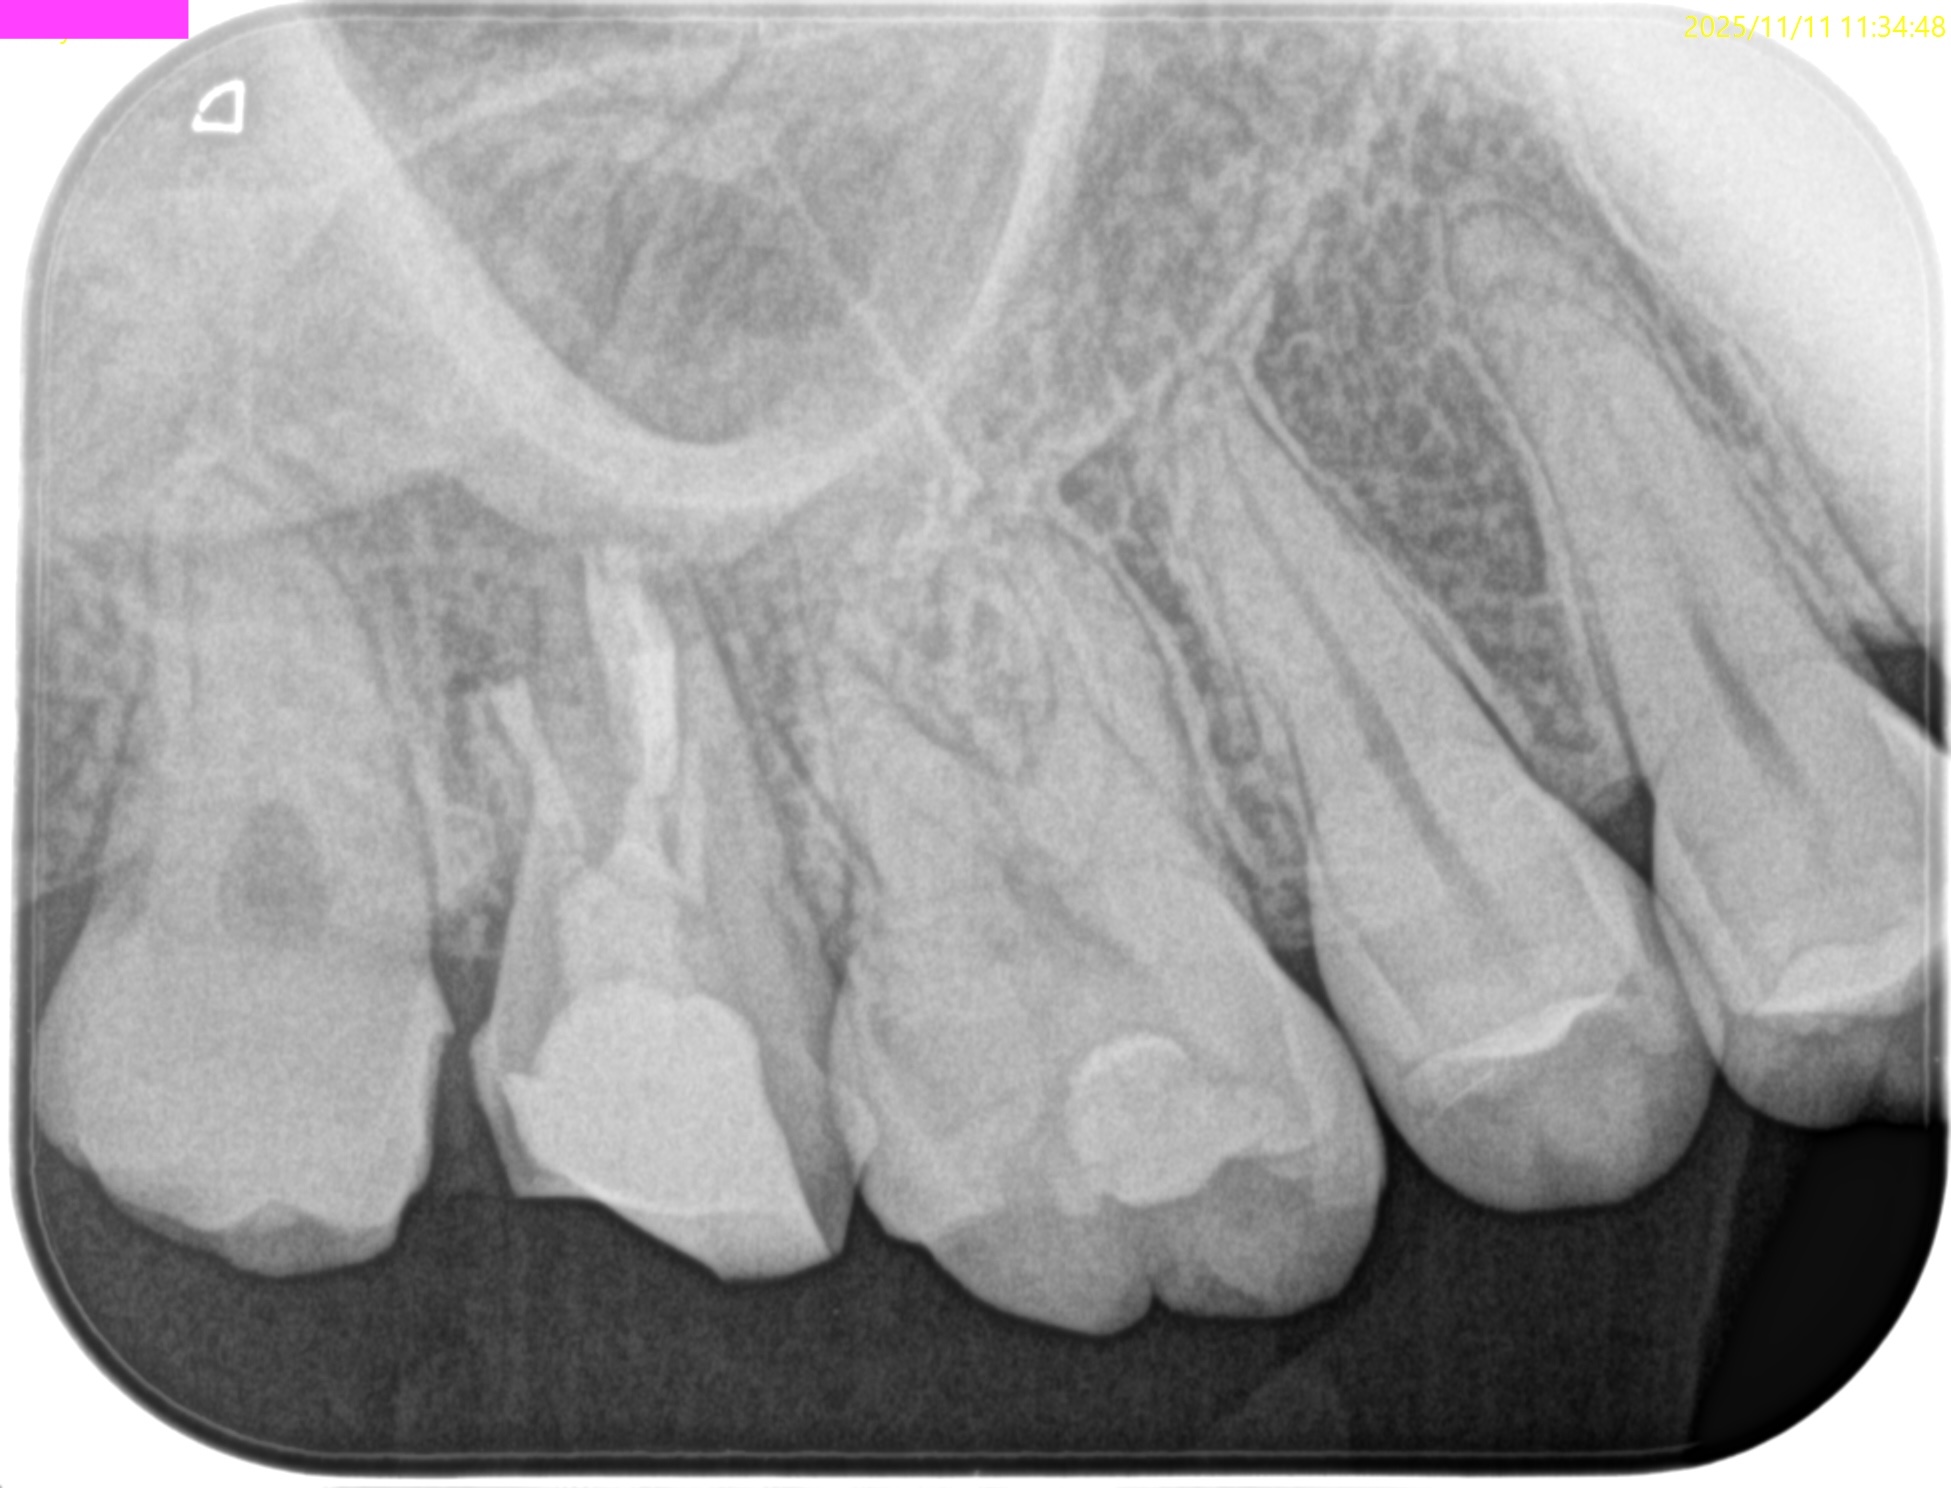

術後にPAを撮影した。

MB

DB

P

B

問題はないだろう。

逆根管充填の状態をイマイチ智度確認した。

MBをもう少し頬側方向に逆根管形成を広げた方がいいのだろうか?と疑問を持ったからだ。

が、

メチレンブルーが染まった場所を私は信じることにした。